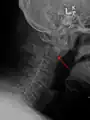

A fracture of the base of the dens as seen on plain X-ray

Axis on X-ray